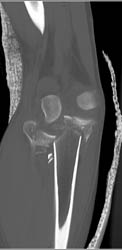

Tibial Plateau Fracture